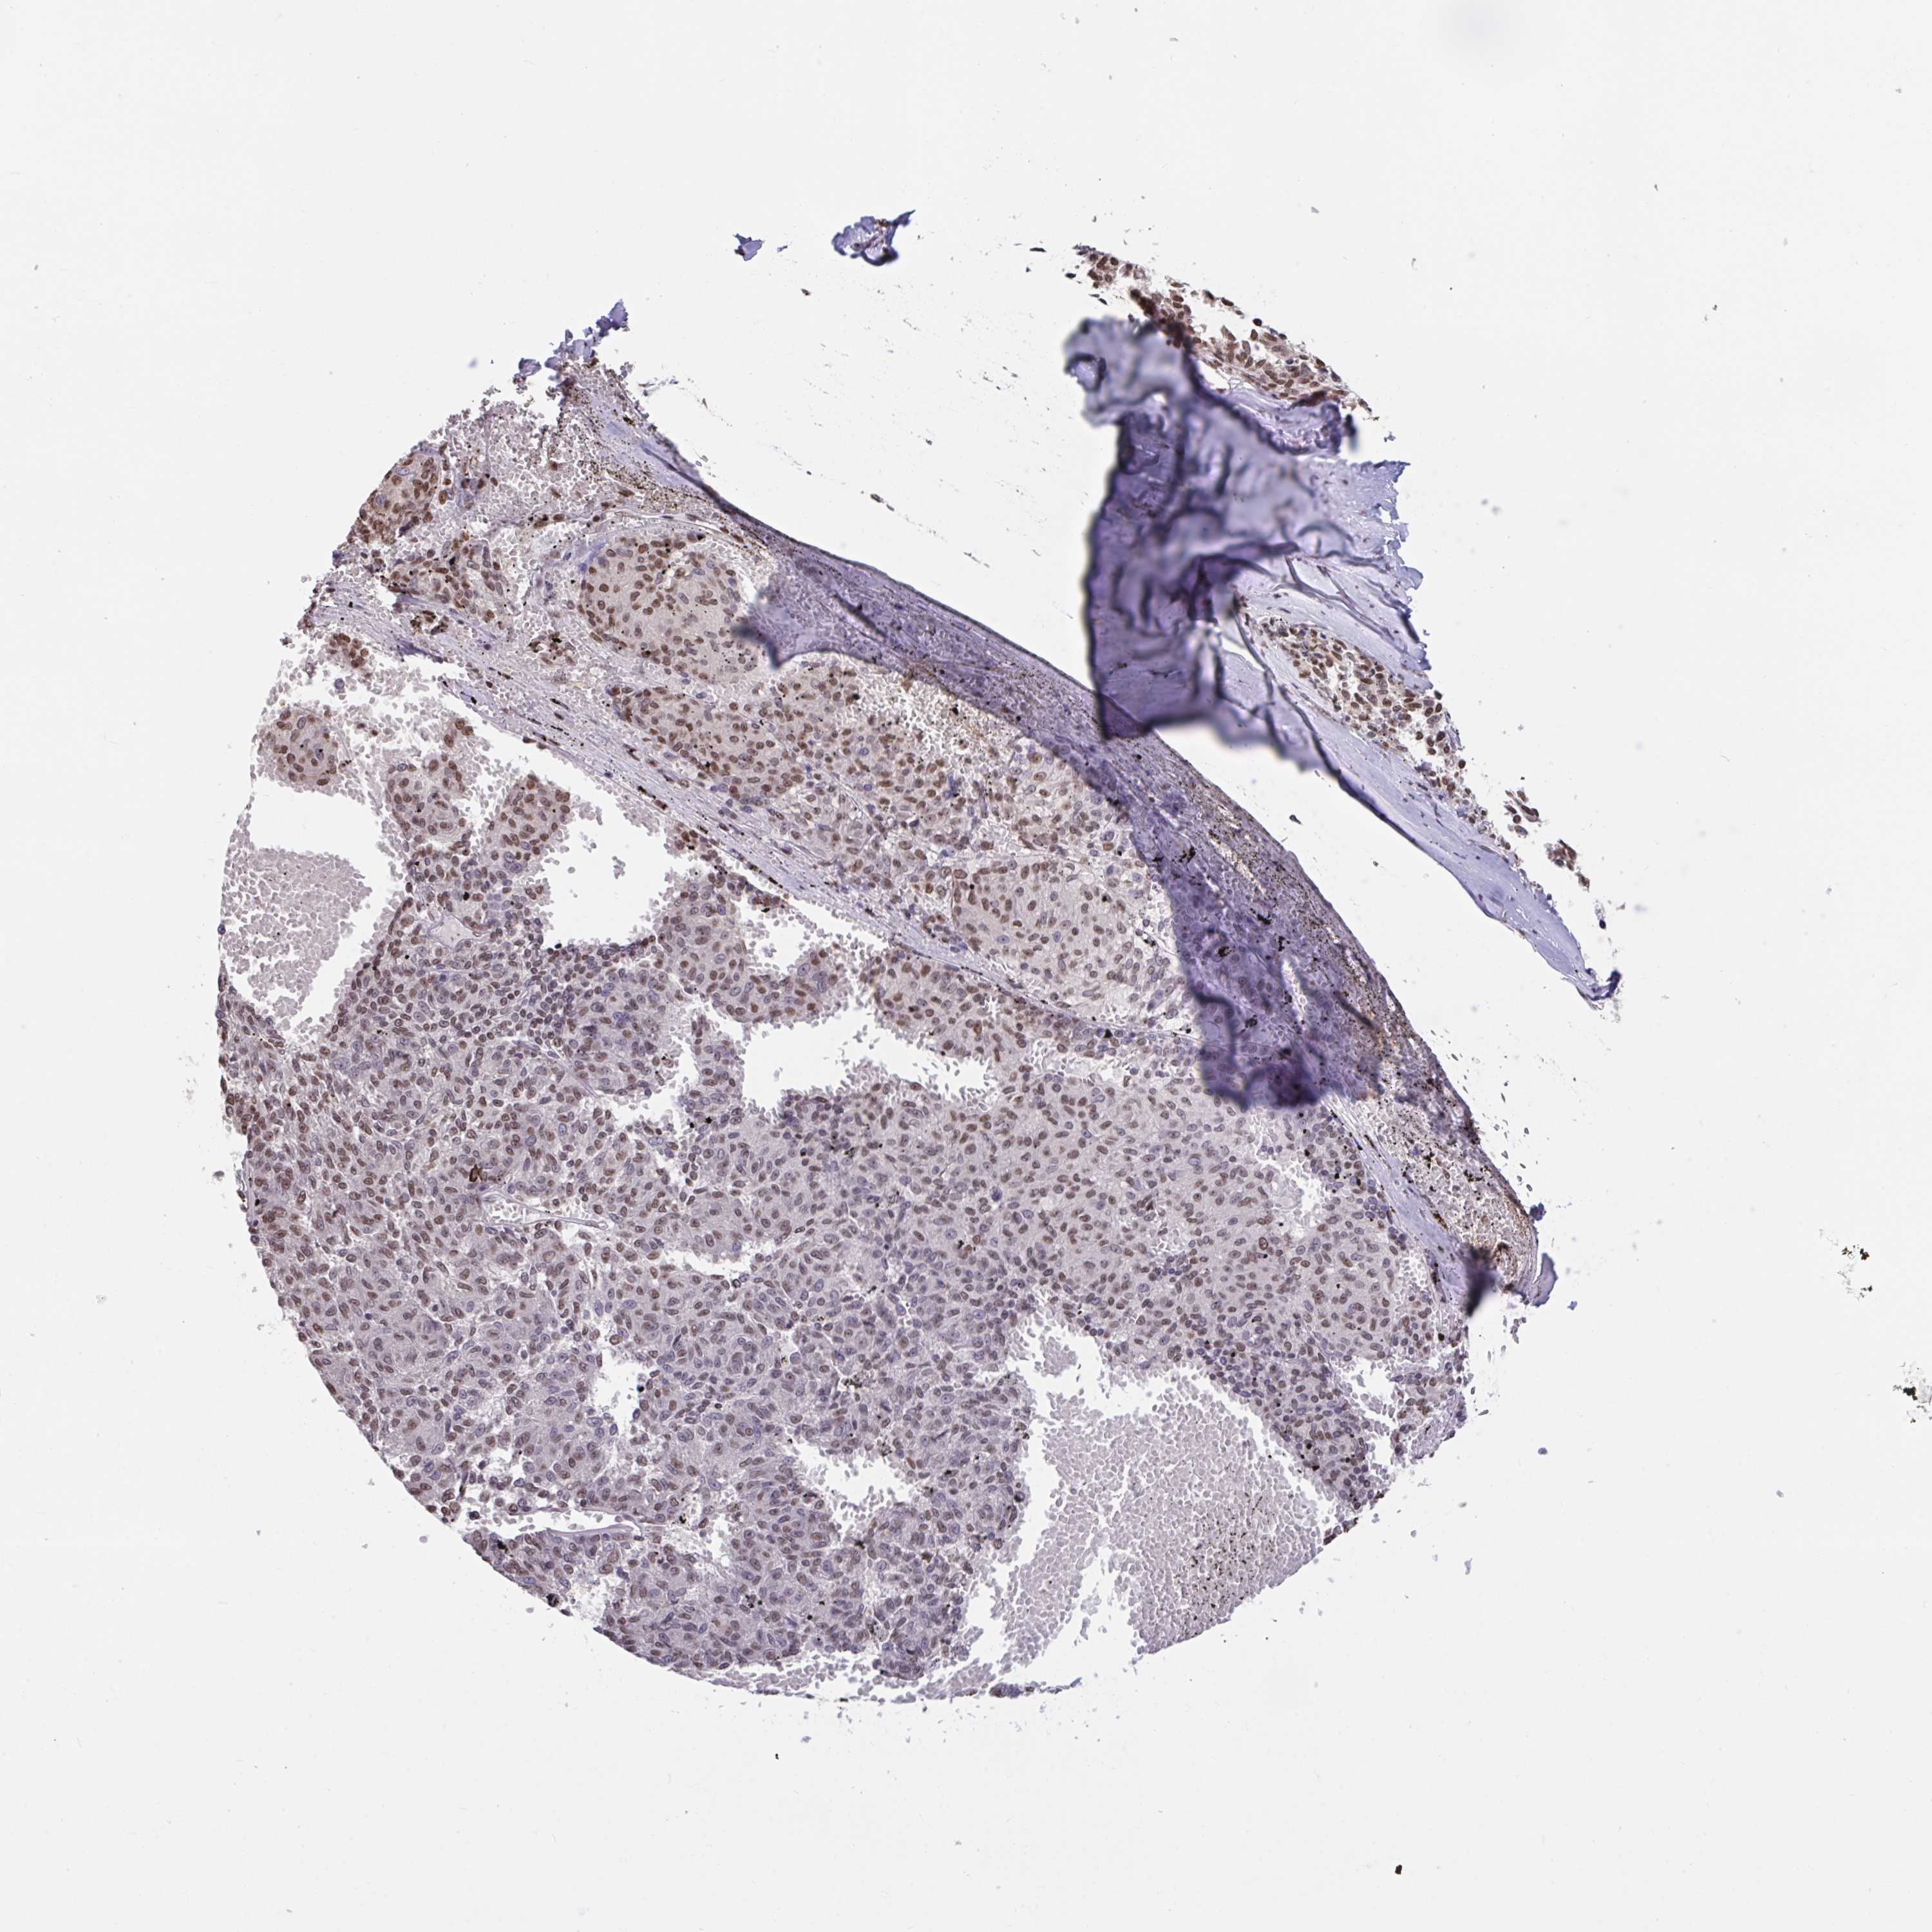

MELANOMA - Protein expressioni

A mouse-over function shows sample information and annotation data. Click on an image to view it in a full screen mode. Samples can be filtered based on level of antibody staining by selecting one or several of the following categories: high, medium, low and not detected. The assay and annotation is described here.

Note that samples used for immunohistochemistry by the Human Protein Atlas do not correspond to samples in the TCGA dataset.

Antibody stainingi

Antibody staining in the annotated cell types in the current human tissue is reported as not detected, low, medium, or high, based on conventional immunohistochemistry profiling in selected tissues. This score is based on the combination of the staining intensity and fraction of stained cells.

Each image is clickable and will lead to virtual microscopy that enables deeper exploration of all samples and also displays staining intensity scores, fraction scores and subcellular localization as well as patient and tissue information for each sample.

Antibody HPA056820

Antibody HPA063147

Staining

High

Medium

Low

Not detected

Intensity

Strong

Moderate

Weak

Negative

Quantity

>75%

75%-25%

<25%

None

Location

Nuclear

Cytoplasmic/membranous

Cytoplasmic/membranous,nuclear

Malignant melanoma, Metastatic site

Malignant melanoma, NOS